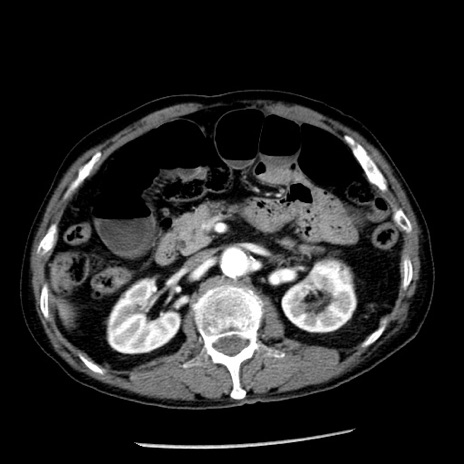

症例26(横断像)

【症例】80歳代男性

【主訴】嘔吐

【現病歴】昨晩2回嘔吐あり、今朝になっても嘔吐あり。来院。

【既往歴】胃潰瘍

【身体所見】意識清明、BT 37.6℃、BP 166/95mmHg、HR 100bpm、SpO2 97%、腹部:平坦・軟、腸蠕動音聴取良好、圧痛なし。

【データ】WBC 21900、CRP 1.46